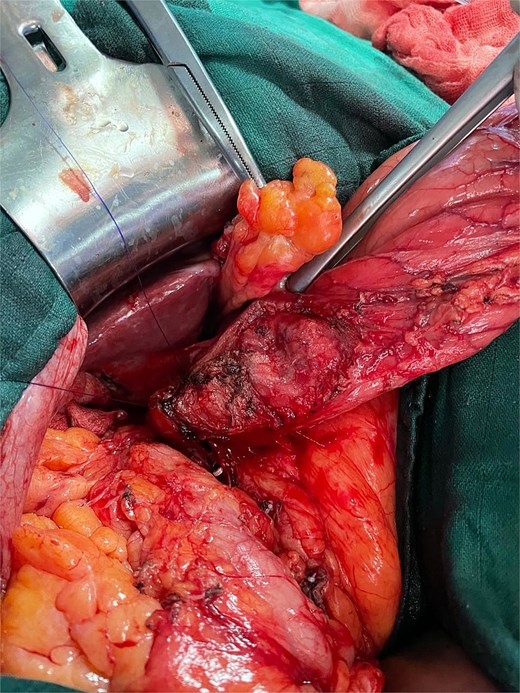

Meticulous dissection allowed liberation of the gallbladder and separation of the pseudocystic gastric formation, with aspiration of purulent content from both the gallbladder and the fistulous tract. Antegrade cholecystectomy was performed with clipping and division of the cystic artery and duct. The fistulous tract was carefully dissected, and partial resection of the affected gastric wall was completed (Fig. 4), followed by closure with 3–0 PDS suture, preserving the gastric mucosa integrity (Fig. 5).

Intraoperative image after resection of the gallbladder and the subserosal gastric cyst.

Frozen section examination of the gallbladder wall fragment showed no evidence of malignancy. The postoperative course was uneventful without complications. Definitive histopathological examination confirmed acute ulcerative and phlegmonous lithiasic cholecystitis with fistulous tract formation, without malignancy criteria.